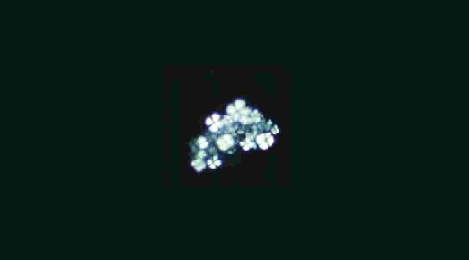

簡易偏向装置を使用して卵円形脂肪体を鏡検したもの。

脂肪球は、Maltese cross と呼ばれる十字が見られる。